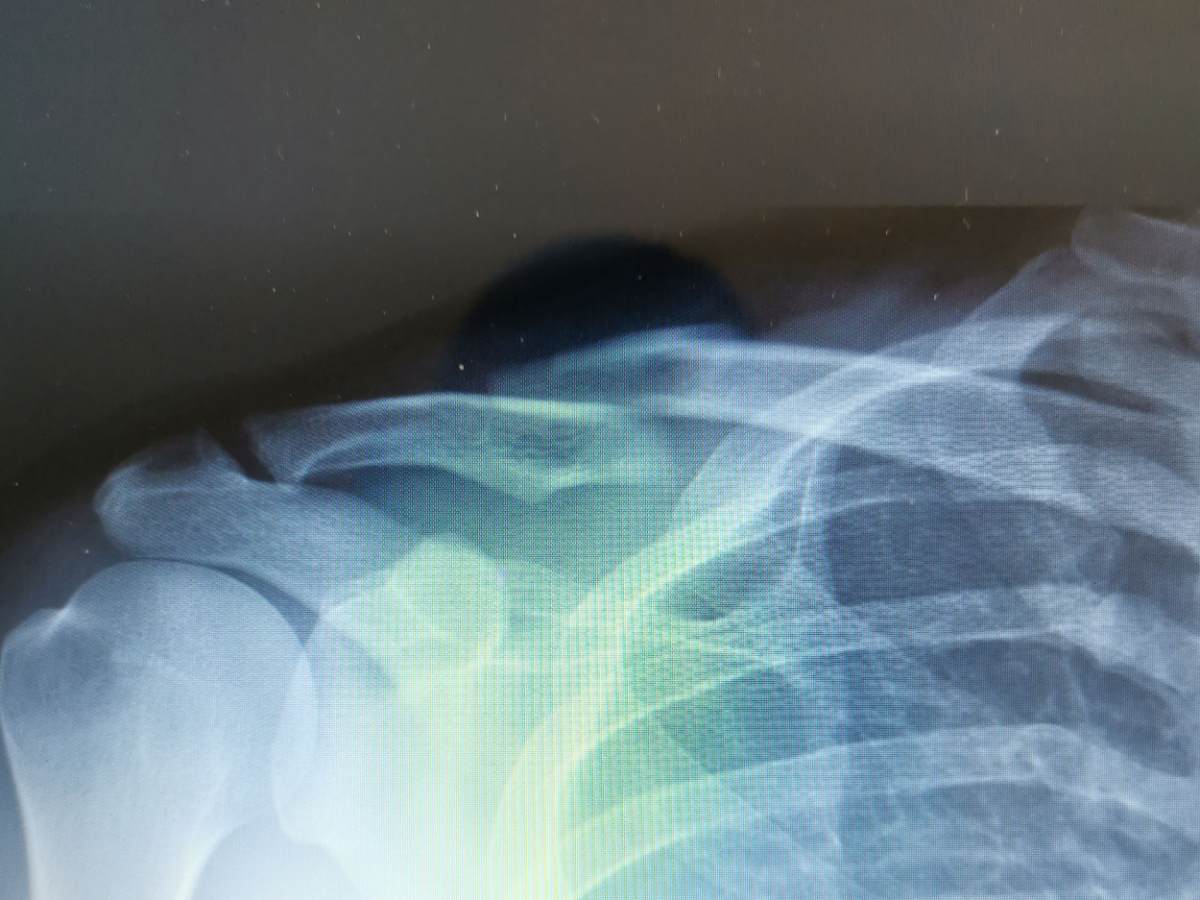

5 tygodni temu złamałem prawy obojczyk z przemieszczeniem. Wolałem nie podddwać się operacji(z kilku względów) i na kwalfikacji do operacji powiedziano mi, że powino się zrosnąć w ortezie. Lekarz prowadzący mówi, że on by zalecał operację, ale możemy też pozostać przy ortezie. Po 5 tygodniach nie widać było na rtg zrostu, odłamy nie przemieściły się.Czasami czuję, że lekko mi się tam rusza jeszcze. Nie palę, chodzę na PM i laser, stosuję mumio i Boneactive complex plus.Nic mnie tam nie boli, nie mam drętwień. Mam w związku z tym kilka pytań: )

Na zdjęciu przed i po operacji.